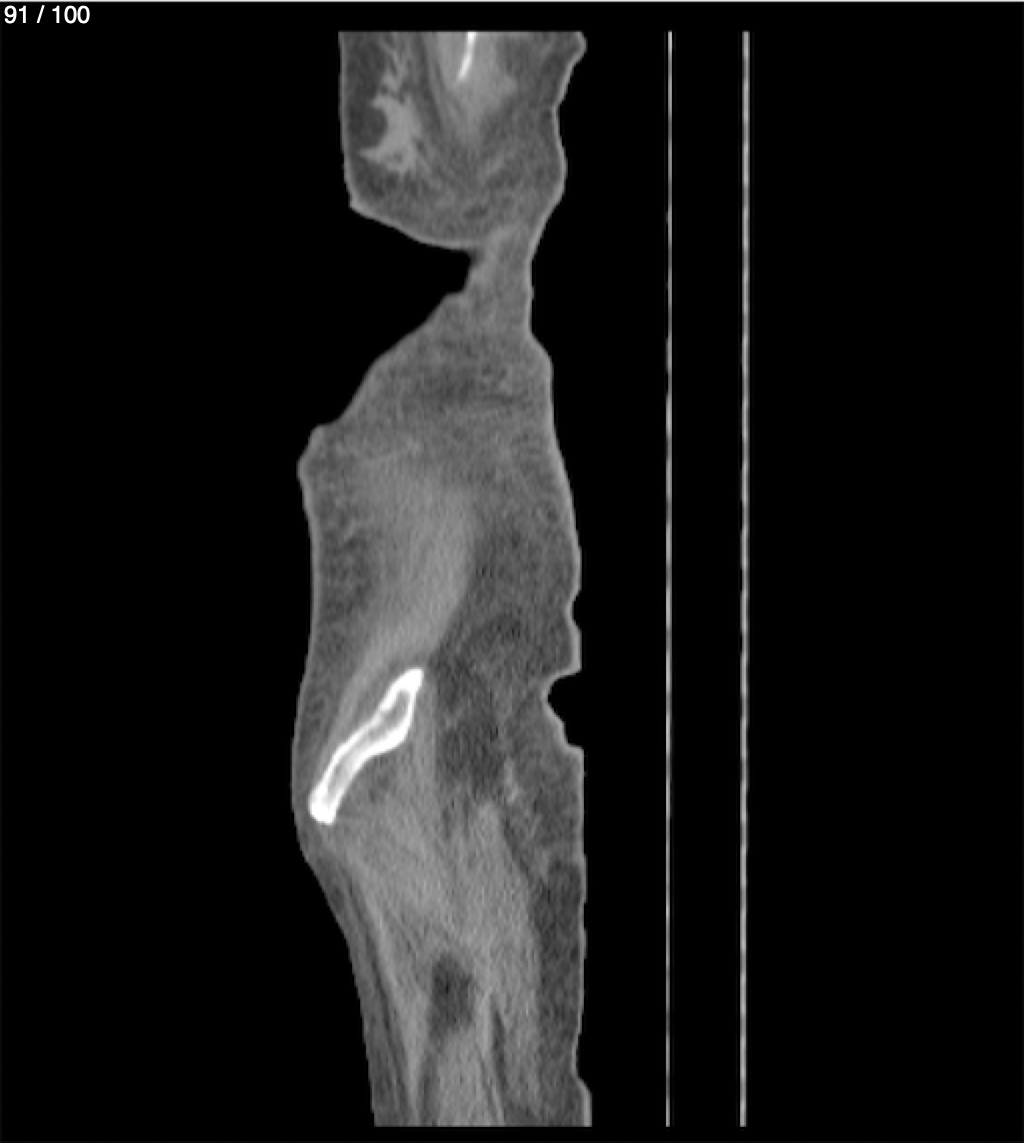

Hilda Geronimo Mendez 60A - T.C Abdomen Simple